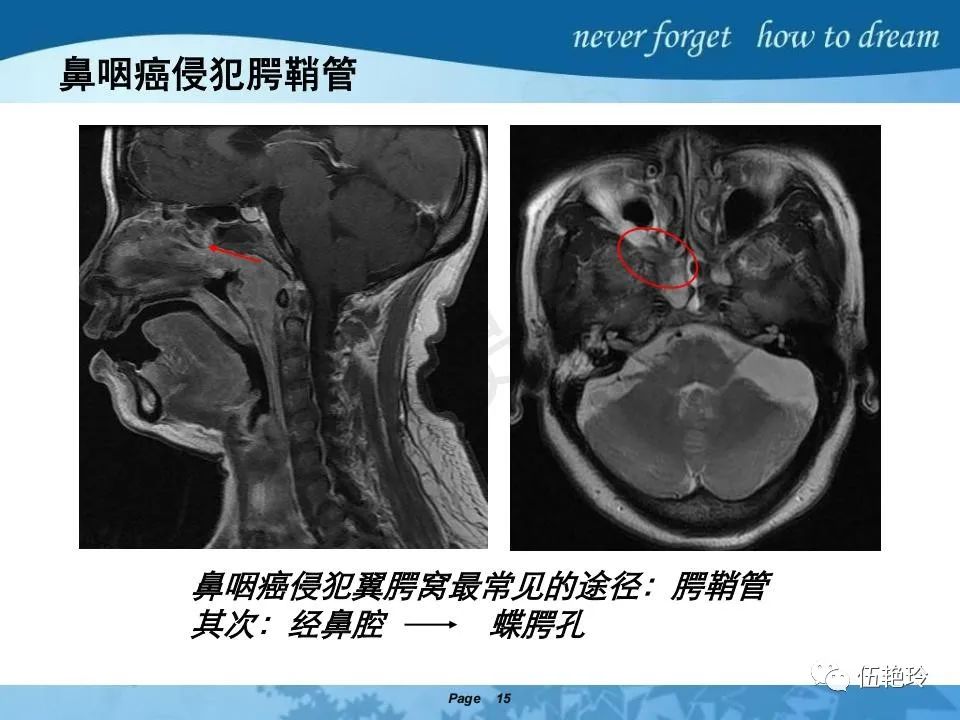

翼腭窝的解剖结构与鼻咽癌侵犯

2.2 鼻咽特有的解剖途径:鼻咽癌原发灶循序进展的总途径:鼻腔(47.8%)→翼腭窝(15.2%)→ 眶下裂(3.2%)→眶尖(1.2%)→海绵窦(0.6%)。

2.31 向上颅内:①鼻咽顶壁→破裂孔(岩尖、斜坡)→蝶窦、海绵窦;②鼻咽顶壁→蝶骨基底部→蝶窦、海绵窦;③鼻咽侧壁→茎突前间隙→蝶骨大翼(卵圆孔)→海绵窦;④鼻咽侧壁→茎突前间隙→翼腭窝→ 颞下窝;⑤鼻咽前壁→鼻腔→翼突、翼腭窝→眶下裂→眶尖→海绵窦;⑥鼻咽前壁→鼻腔→上颌窦、筛窦;